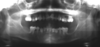

3 radiographic findings of cleidocranial dysplasia

A

• Prolonged retention of deciduous teeth

• Mulitple unerupted supernamary teeth resembling premolars

• Maxillary hypoplasia